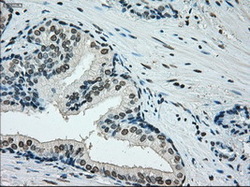

- Immunohistochemical staining of paraffin-embedded Adenocarcinoma of colon tissue using anti-ERCC1 mouse monoclonal antibody. (Dilution 1:50).